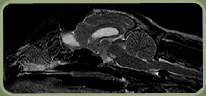

Canine with Syringomyelia.

In the MRI perfomed on this Spaniel with Syringomyelia, you can see the hindbrain poking down through the foramen magnum. Several wide syrinxes can be seen in the cervical spinal cord (white).